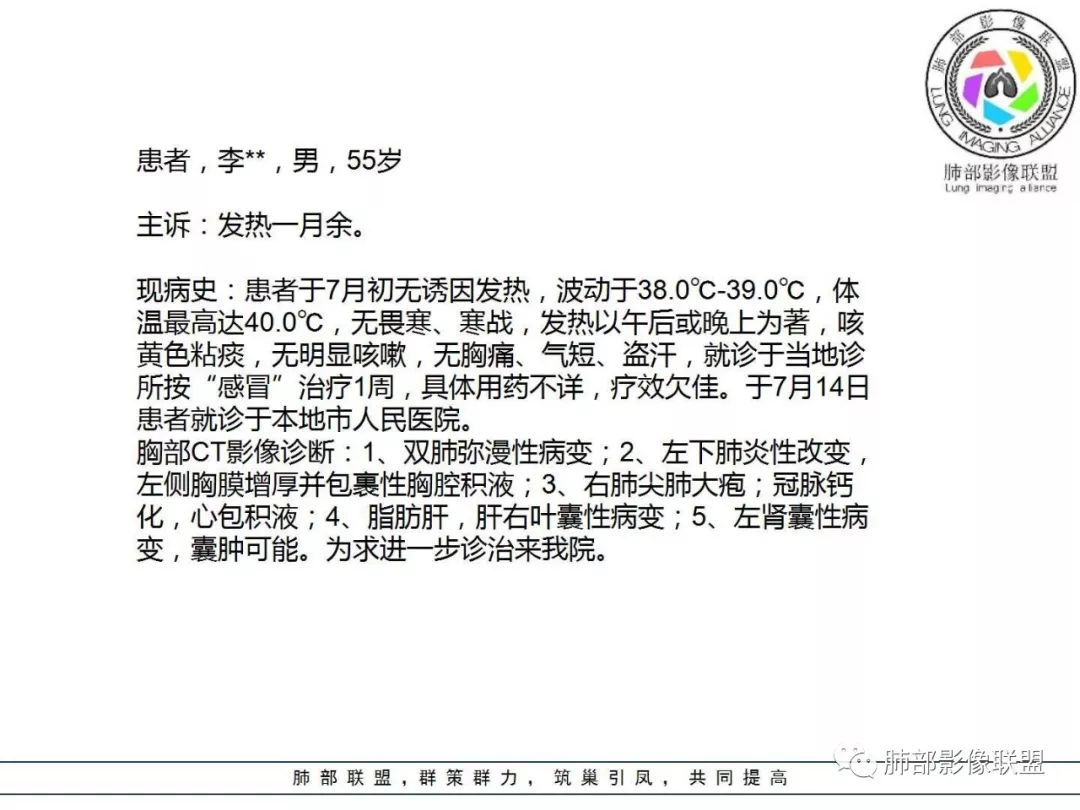

1. 老年男性,发热为主诉,体温38°-39°,发热以午后及晚上为主,伴黄痰,CRP增高,临床病史支持感染性病变;

2. 肺气肿背景(小叶中心性肺气肿);双肺多发病灶整体沿血管支气管束及胸膜下分布,以上叶及下叶背段分布为主,有实变及GGO,边界清楚,有树芽,小叶间隔及中央间质增厚,叶间裂见到多发结节,部分支气管不规则牵拉扩张,提示病灶纤维化明显,结合临床病史,考虑病灶为间质性感染,肺门及纵隔内有钙化淋巴结,小叶间隔结节,考虑淋巴道增值性疾病可能,综合常规要怀疑间质性肺结核。